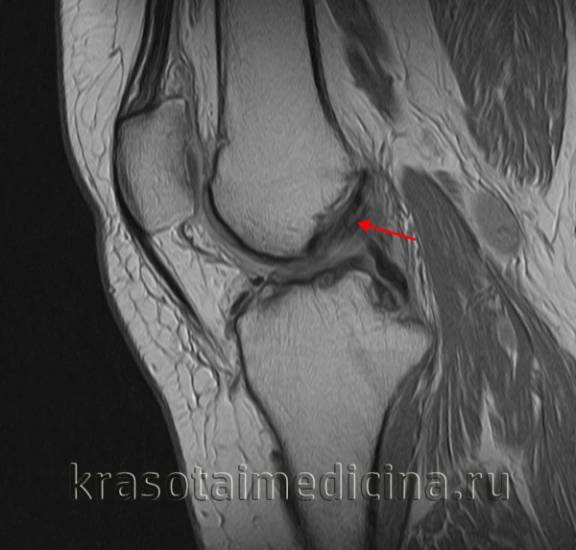

МРТ коленного сустава показывает повреждение (отек, разволокнение, частичный разрыв) передней крестообразной связки.